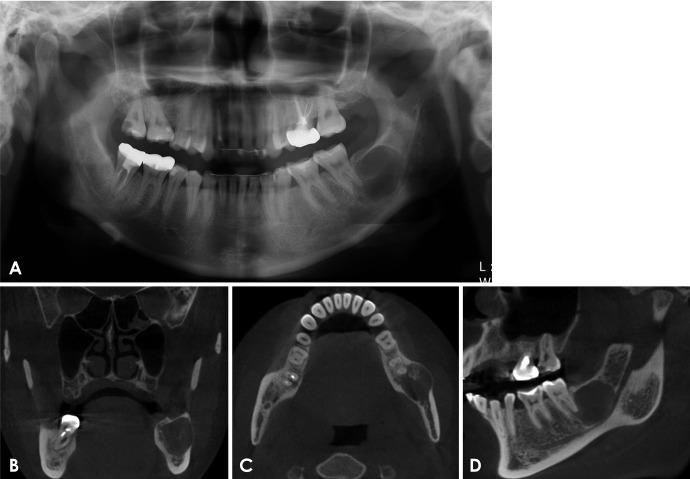

Ossifying fibroma is a slow-growing benign neoplasm that occurs most often in the jaws, especially the mandible. The tumor is composed of bone that develops within fibrous connective tissue. Some ossifying fibromas consist of cementum-like calcifications, while others contain only bony material; however, a mixture of these calcification types is commonly seen in a single lesion. Of the craniofacial bones, the mandible is the most commonly involved site, with the lesion typically inferior to the premolars and molars. Ossifying fibroma of the jaw shows a female predominance. Some reports of ossifying fibroma have been published in the literature; however, this report continues the research on this topic by detailing 3 types of ossifying fibroma findings on panoramic radiographs and cone-beam computed tomographic images of 4 patients. The radiographs of the presented cases could help clinicians understand the variations in the radiographic appearance of this lesion.

骨化性纤维瘤是一种生长缓慢的良性肿瘤,最常发生于颌骨,尤其是下颌骨。该肿瘤由在纤维结缔组织内形成的骨组织构成。一些骨化性纤维瘤由类牙骨质钙化组成,而另一些仅含有骨质材料;然而,在单个病变中通常可见这些钙化类型的混合。在颅面骨中,下颌骨是最常受累的部位,病变通常位于前磨牙和磨牙下方。颌骨骨化性纤维瘤以女性居多。文献中已发表了一些关于骨化性纤维瘤的报告;然而,本报告通过详细描述4例患者全景X线片和锥形束计算机断层扫描图像上的3种骨化性纤维瘤表现,继续对该主题进行研究。所呈现病例的X线片有助于临床医生了解该病变X线表现的差异。